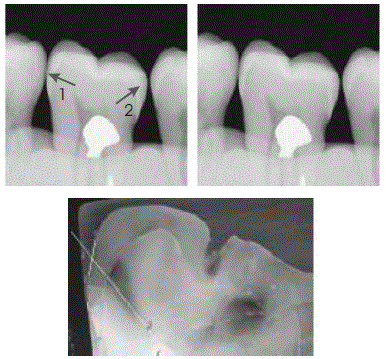

Caries Research, v. 38, p. 34-8, 2004.

As imagens radiográficas ilustradas acima são relativas a uma mesma situação clínica e seu correspondente histológico. Considerando essas imagens, julgue os itens a seguir.

I A imagem radiográfica da superfície distal do molar apresenta

lesão cariosa de esmalte

II A imagem radiográfica da superfície mesial do molar

apresenta lesão em esmalte e dentina

III A lesão em dentina, presente na situação clínica acima, corresponde a lesão cavitada.

IV Há tratamento não-operatório adequado para a situação clínica acima.